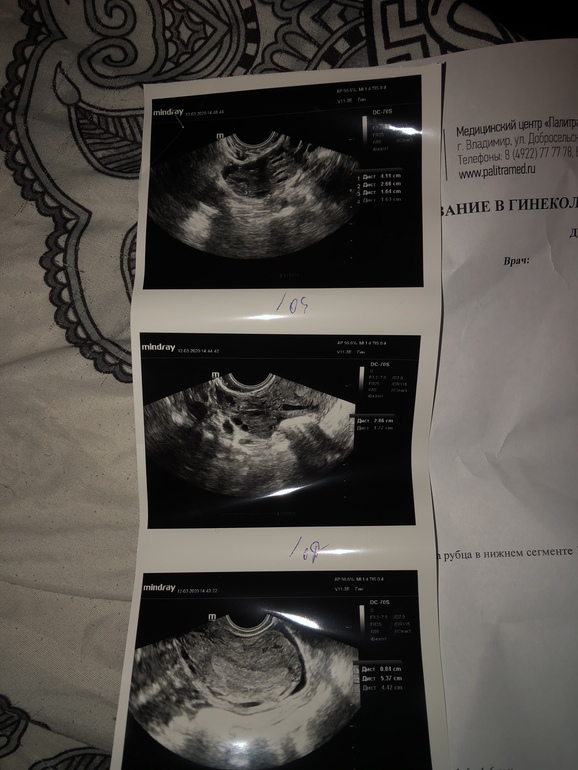

Всем доброго вечера, ситуация такая у меня 12 ДПО тесты начала мочить на 10 ДПО т.к почувствовала что получилось. Сегодня сдала на ХГЧ ( результат будет завтра). И сделала УЗИ чтобы исключить внематочную( 2 года назад поставили непроходимость труб). Может кто делал узи на таком сроке какие показатели были что то увидели? Ходила не к своей Г т.к хотелось узнать побыстрей на узи толком ничего не сказали и ничего не увидели.

Если бы была беременность,то должна была быть немного увеличена матка, жёлтое тело бы было не в стадии"регресса".И эндометрий не 3 мм,а больше гораздо.Но вдруг я ошибаюсь🤔. ХГЧ все покажет .

там с эндометрием странность.3 см, а не мм

Да мне кажется она вообще толком не смотрела ничего , и эндометрий вообще от балды написан

А по поводу внематочной. Слишком тонкий эндометрий у вас и при внематочной он как раз такой. У меня был 5мм. И к сожалению, динамика на тестах слабоватая. Сдавайте хгч. Следите. У меня внематочную увидели при хгч около 400. Трубу удалили(((

Давайте рассуждать логически. Чтобы исключить вб, вам надо увидеть плодное яйцо. И определить, собственно, его локализацию (маточная или внематочная беременность). В среднем, ПЯ на УЗИ видят, когда ХГЧ переваливает за 1000. В этот момент полоски на тестах уже довольно яркие. Не призрачные, точно. По срокам это, ориентировочно, 4,5-5 недель (или 17-21 ДПО). Идти раньше смысла нет: вам могут предположить беременность по косвенным признакам, и это будет максимально возможный результат, с достоверностью 50/50.

А УЗИ у вас странное, да. Такое ощущение, что смотрели на отвяжись.

Само описание узи смущает: эндометрий всего 3мм (это самое начало 1 фазы норма) плюс ЖТ в регрессии😳

Просто Вы очень рано пошли на УЗИ. А так, меня только эндометрий смущает, 0,3 не может быть при маточной Беременности. Я бы сходила к нормальному узисту, на хорошем аппарате.